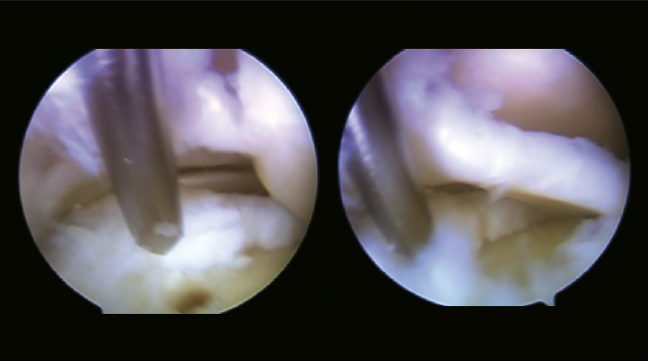

En condiciones de asepsia y esterilidad, mediante anestesia intrarraquídea y bloqueo del plexo poplíteo, en decúbito supino con el pie en suspensión sin tracción, se realizó artroscopia del tobillo derecho mediante portales artroscópicos anteromedial y anterolateral en la que se visualiza lesión condral de base medial en la zona Raikin 6, confirmando la lesión valorada en la TAC y la RM. Se objetivó osteofito en la tibia anterior distal y se realizó su escisión a través de los portales convencionales.

Figura 4. Acceso artroscópico a través de la sindesmosis a la lesión osteocondral. Nanoperforaciones. Se observa lesión condral inestable con lengüeta de base medial.

En un segundo tiempo se realizó un portal de trabajo mediante acceso transindesmótico anterior a 4 cm desde la línea tibioastragalina (Figura 3), previa disección roma en la piel, valorando la accesibilidad desde este punto de entrada a la lesión osteocondral previamente con una aguja de venopunción de 21 G × 1 1/2” (0,8 × 40 mm) y una vez localizado el punto de entrada con aguja de Kirschner de 1,5 mm de diámetro. Posteriormente, se realizaron nanoperforaciones en el hueso subcondral (Figura 4), reinserción del cartílago con implante reabsorbible de copolímero poliláctico (SmartNail®, ConMed Linvatec, Largo, FL) (Figura 5).